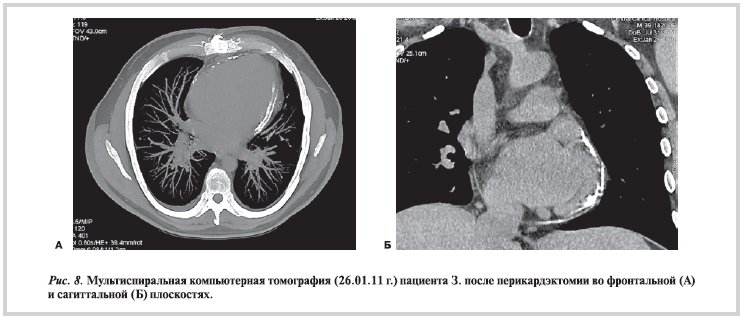

По данным рентгенографии грудной клетки, легочные поля без «свежих» очаговых и инфильтративных теней с умеренно выраженным пневмосклерозом. Корни легких не расширены. Сердце с нерезким увеличением левого желудочка (ЛЖ), «талия» сердца сглажена. Обращало внимание склерозирование листков перикарда. Аорта без особенностей (рис. 1).

По данным МСКТ грудной и брюшной полостей отмечалась заметная положительная динамика — явления полисерозита практически не определялись (за исключением минимального количества жидкости в полости перикарда и правой плевральной полости). Внутригрудные ЛУ не увеличены в размерах, но увеличены количественно. Внутрибрюшные ЛУ не увеличены. Умеренное увеличение печени (рис. 8).